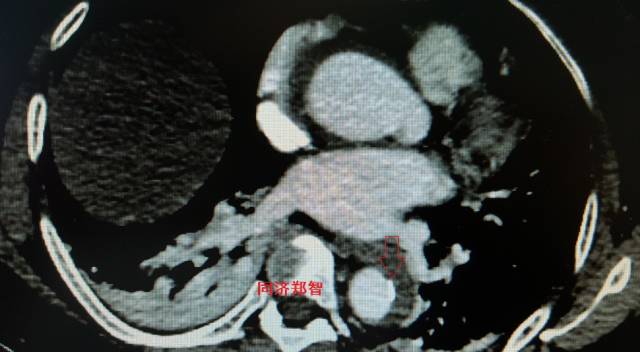

平扫CT提示主动脉弓层面及右肺动脉层面均可见主动脉血管腔内的内膜片影(红色箭头所示),CTA显示为A型主动脉夹层。

图8-11